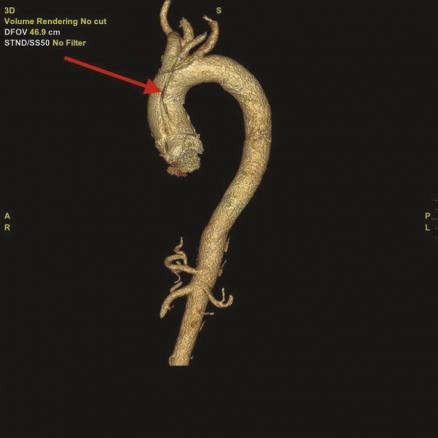

Cet homme de 55 ans, sans antécédent, avait appelé le 15 pour une douleur thoracique irradiant dans la mâchoire et des paresthésies du bras droit, après un effort de marche. À l’examen la pression artérielle était de 165/85 mmHg symétrique, les pouls étaient symétriques, et il n’y avait pas de déficit moteur des 4 membres. L’électrocardiogramme montrait un léger sous-décalage du segment ST en DIII et AvF. Le médecin du SMUR retenait le diagnostic de syndrome coronaire aigu « non ST+ » et orientait le patient vers une unité de soins intensifs cardiologiques où la tomodensitométrie thoracique (fig. 1) révélait finalement une dissection aortique de type A étendue de la racine de l’aorte jusqu’à l’ostium de l’artère carotide primitive gauche (fig. 2).